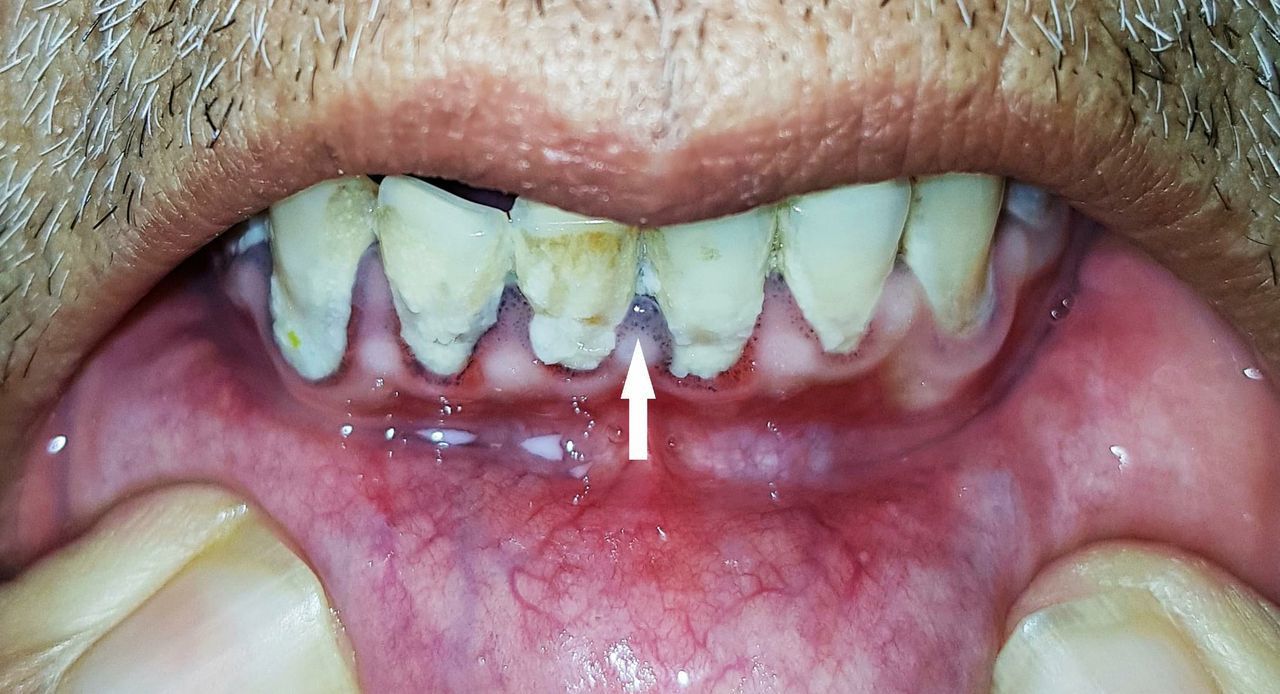

The image above shows a bluish line on the gums. This is referred to as Burton's line and it is one of the signs seen in lead poisoning. Lead is a heavy metal toxic to man. The most severe effects are seen on the central nervous system, the presentation of which ranges from insomnia and tremors to significant cognitive decline and convulsions. It leads to microcytic anemia. Other signs and symptoms include colicky abdominal pain, renal dysfunction, parasthesias, neuropathies and even reproductive problems. The condition can be diagnosed by measuring serum lead levels and observing basophilic stippling in peripheral blood smear. While treatment largely involves chelation, lead poisoning is preventable in most cases. This involves avoidance of certain types of paints, minimizing the use of lead containing pipes, jewelry and utensils, and ensuring that your water supplies are safe. Image via: https://casereports.bmj.com/content/12/4/e227954